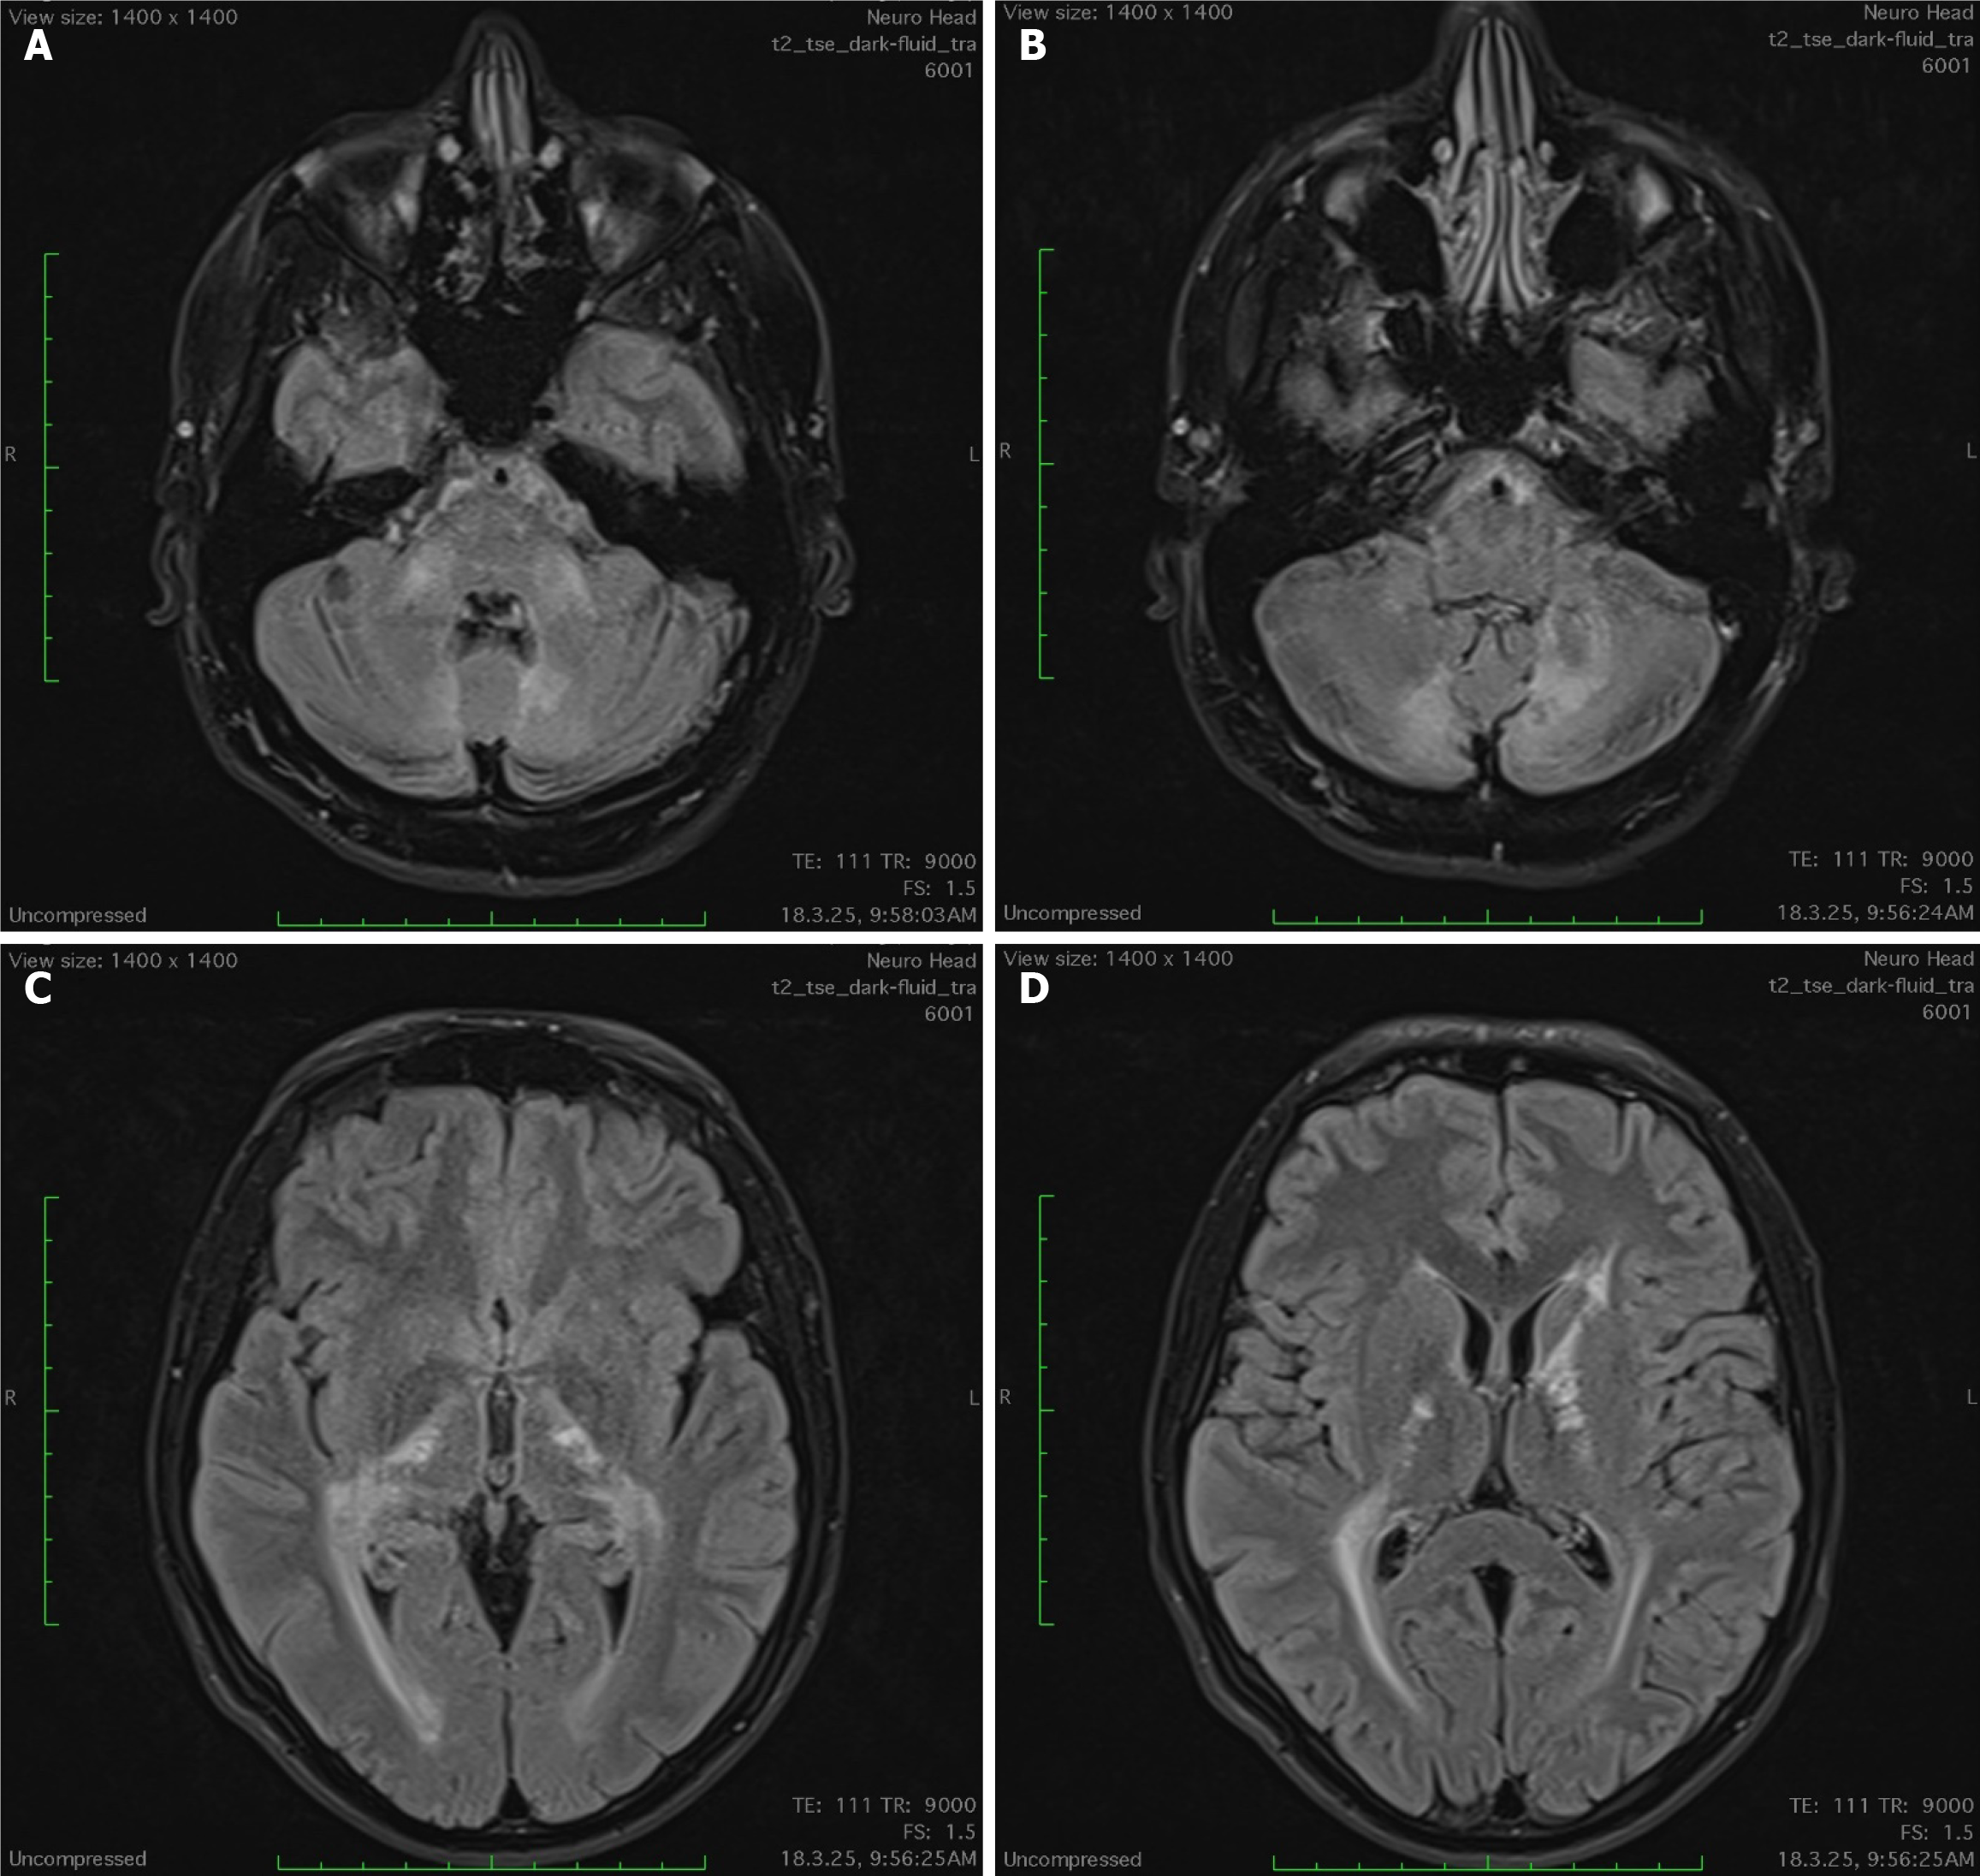

Figure 1 Brain magnetic resonance imaging showing bilateral nearly symmetrical white matter hyperintensities on T2-weighted, fluid-attenuated inversion recovery sequences.

A and B: Infratentorial images; C and D: Supratentorial images.